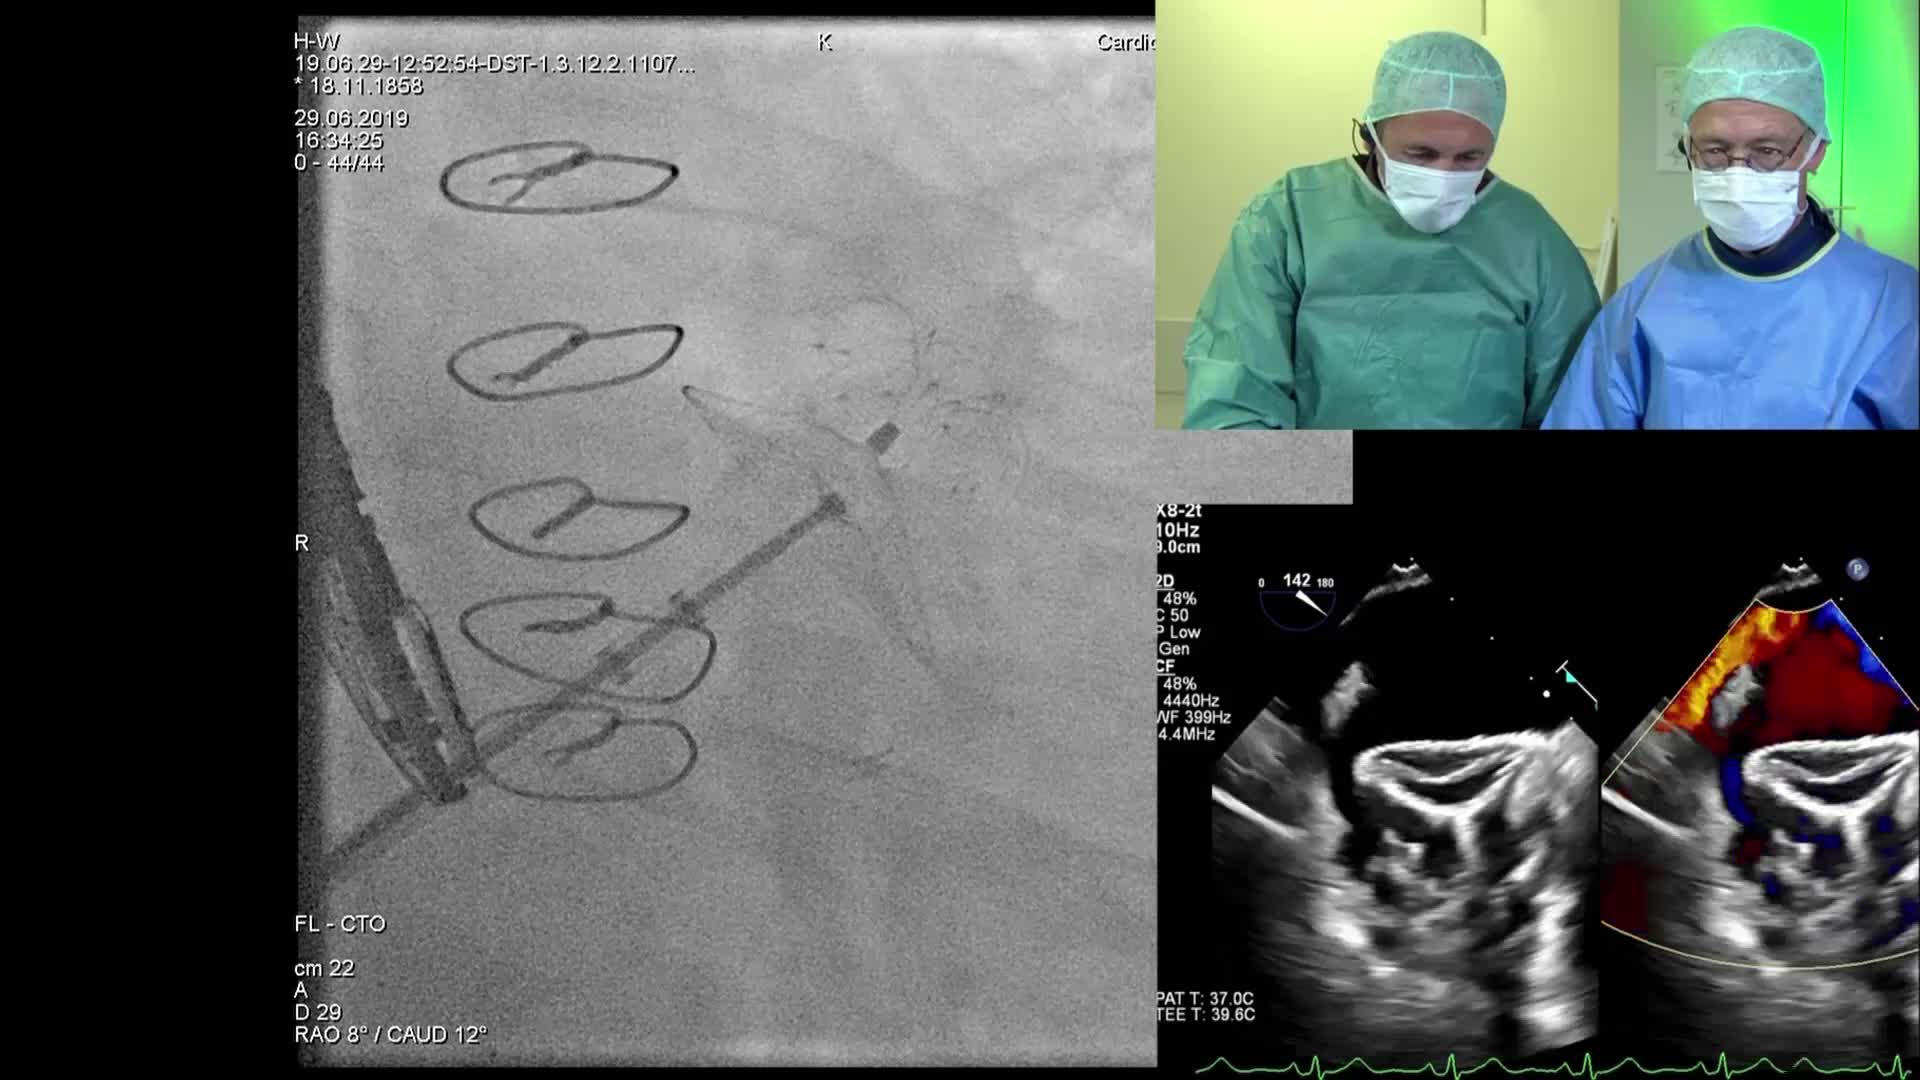

Cathlab Live Cases